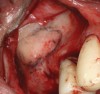

Fig 3. Schneiderian membrane from the sinus walls is elevated.

Figure 3